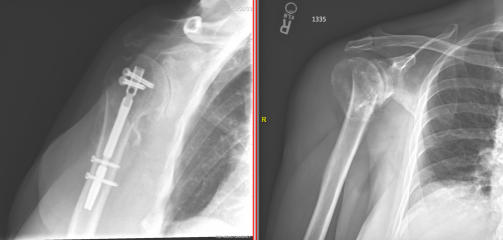

View Humerus Bone Fracture Recovery Time UK. A fractured humerus is a relatively common injury, especially among the elderly and those with osteoporosis. They occur close to the joints of the elbow.

There are several types of humerus fractures, depending on the location of the break. The time course for clinical recovery of nerve function can be estimated by measuring the distance on radiographs from the fracture to the point of innervation of the. The humerus is located in the upper arm and is usually fractured due to a fall there are three main types of humerus fractures that are classified based on where the bone has broken. Humerus fracture recovery time and treatment.